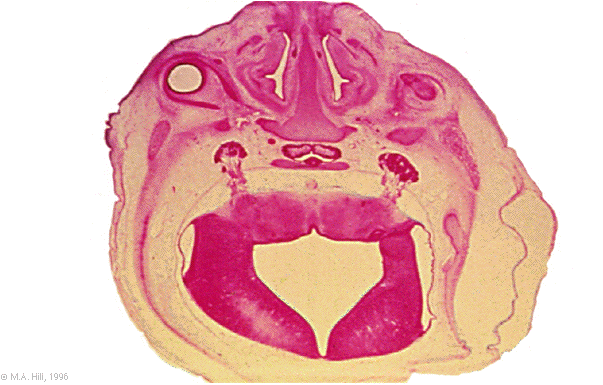

Hum B2